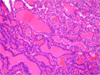

Case presentation: We described a case of metastatic follicular thyroid carcinoma to the mandible presenting with pain and loosening of teeth in a 70 years old female patient leading to extraction of the loose teeth.